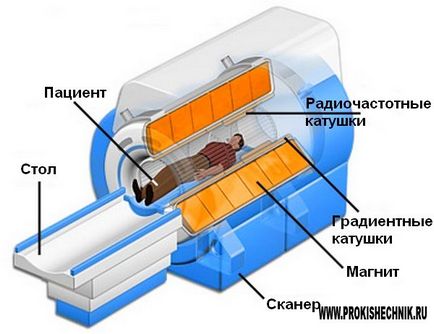

A működési elve az MRI

Abban a vizsgálatban, testrészben MRI beteg jár, mint lüktető egyenáramú mágneses erőtér és rádiófrekvenciás sugárzás. Ezek alkotják a speciális eszköz - szkennert. Néhány másodpercen belül, akkor a készülék küld egy bizonyos részét a RF pulzus okozza a swing és a lép rezonancia hidrogénatomok a szervezet sejtjei. További speciális berendezések összegyűjti a beérkezett jelzéseket, feldolgozza azokat, és kiadja a háromdimenziós képet a kémiai szerkezet a szövet a környéken.